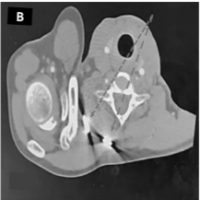

Physical examination revealed visible deformity of the ankle, including hindfoot varus and cavus with severely limited ankle joint range of motion and minimal subtalar joint motion compared to the contralateral limb. Pain and functional status were assessed using the Visual Analog Scale (VAS) and American Orthopaedic Foot and Ankle Society (AOFAS) scores pre and postoperatively. Radiographs obtained during follow-up showed collapse of the talus. A computed tomography scan performed subsequently demonstrated union of the medial and lateral malleoli, with non-union of the talus and sclerosis of the talar dome consistent with AVN (Fig. 2).

Figure 2: Pre-operative computed tomography images obtained immediately prior to revision surgery showing non-union of the talus with sclerosis of the talar dome consistent with avascular necrosis, while the medial and lateral malleoli demonstrate union.